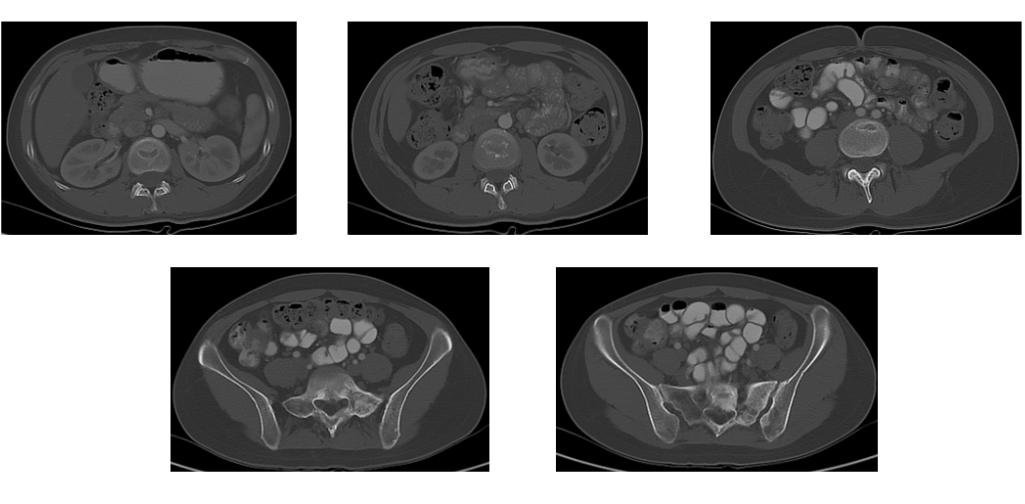

完善CT示 :部分腰骶椎、右侧耻骨,左髋骨见多发结节状高密度影,考虑骨转移;未见其它转移征象。

初步诊断 :右乳癌术后(ypT1N0M0,IA期)多发骨转移(IV期)